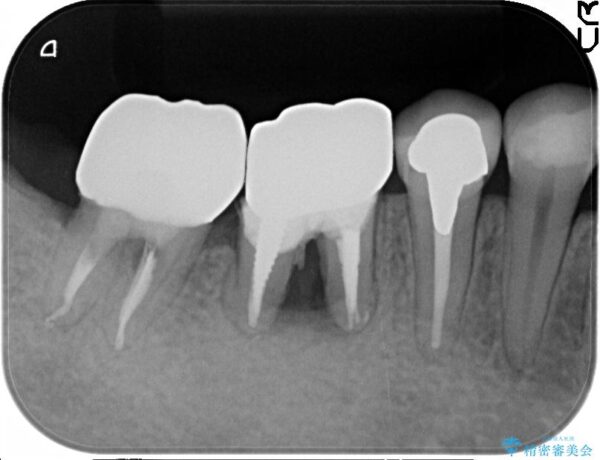

X線写真検査より、クラウンや銀歯の下で歯に大きな虫歯が発生し、抜歯を余儀なくされる状況でした。

虫歯に伴い歯槽骨の吸収も見られたので造骨後、インプラントを用いて咬合機能を回復します。

治療前

遊離歯肉移植術を伴うインプラント治療 治療前画像 遊離歯肉移植術を伴うインプラント治療 治療前画像 遊離歯肉移植術を伴うインプラント治療 治療前画像 遊離歯肉移植術を伴うインプラント治療 治療前画像 遊離歯肉移植術を伴うインプラント治療 治療前画像 遊離歯肉移植術を伴うインプラント治療 治療前画像 遊離歯肉移植術を伴うインプラント治療 治療前画像 遊離歯肉移植術を伴うインプラント治療 治療前画像 遊離歯肉移植術を伴うインプラント治療 治療前画像